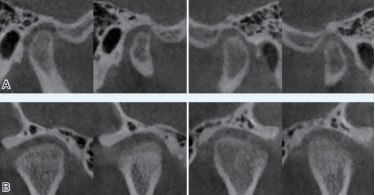

CBCT具有扫描速度快,空间分辨率高,辐射剂量小,图像伪影小等优点,其对颌面、牙齿、骨骼的良好成像效果,高质量的三维立体图像,图像精度提高,无几何失真,可以进行清晰的实际测量。此外,放射剂量更小,尽管高于普通平片,但由于能够满足传统检查无法实现的诊断需求,因此,被广泛用于口腔科临床诊断和治疗,有助于临床做出精确诊断及临床治疗计划的制定与实施。适应症分别有:正畸:三维头影测量、气道分析、正畸种植支抗定位。修复种植:评估患者的骨质、骨量、并掌握下颌神经管、鼻底上颌窦等重要的位置,可以方便设计和制作手术导板。牙体牙髓:疑难根管、遗漏根管及钙化根管的影像诊断。牙周:牙周病的评估。口腔颌面外科:埋伏牙、阻生牙、多生牙的三维定位、颌面部骨折、颞下颌关节紊乱的诊断。

(口腔颌面外科医生可以通过CBCT观察患者两侧颞下颌关节的情况)